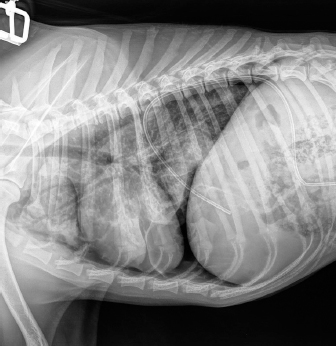

Case details for each of the five dogs included in the study are listed in Table 1. The etiology of the pneumothorax were congenital pulmonary bullae in two dogs, traumatic in one (road traffic accident), lungworm infection in one, and unknown in the remaining dog. Dog number 1 presented a large pulmonary bulla in the right cranial pulmonary lobe (Fig. 1). Dog number 2 presented four bullae: two in the medial aspect of the left cranial lung lobe (17 mm each), one in the caudal aspect of the left caudal lung lobe (26 mm), and another in the caudal border of the left caudal lung lobe (36 mm) (Fig. 2). Dog number 3 presented a large bulla measuring 33 mm in the medial aspect of the right middle lung lobe and around 10 blebs measuring from 3 to 6 mm in the ventral border of both right and left cranial lung lobes. Dog number 4 developed multiple small bullae and a larger one measuring over 10 cm, 24 hours after treatment of lungworm with spot on Imidacloprid and Moxidectin, which were responsible for a moderate unilateral pneumothorax (Fig. 3). Despite the severity of the pneumothorax, dog number 5 did not show any lesions on the computed tomography (CT) scan that could clearly explain its origin. Only one chest tube was placed in dogs 1, 2, 3, and 4. Two were placed in dog 5.

Fig. 1. CT transverse image of the thorax of the dog number 1 with pneumothorax showing a large pulmonary bulla in the right cranial lung lobe (arrow).